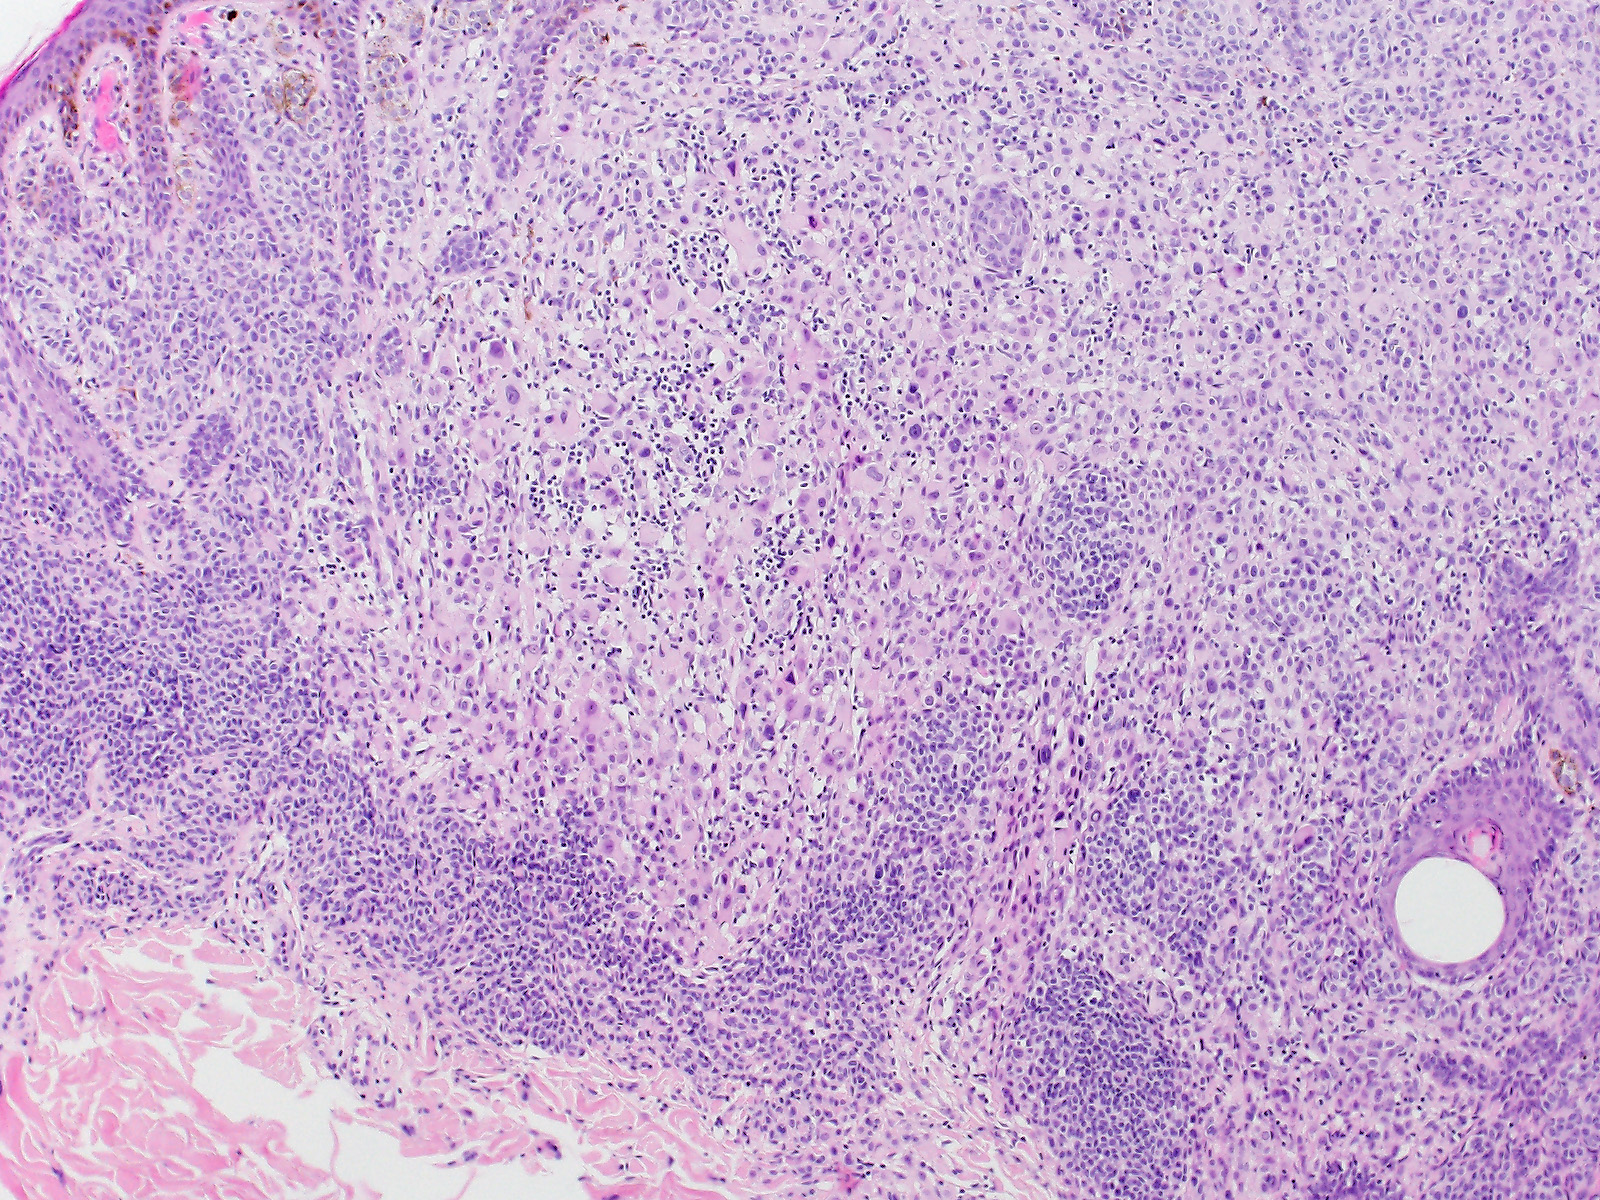

Wiesner Naevus

Biphänotypischer, überwiegend intradermaler Naevus mit einer kleinzelligen gewöhnlichen Naevuskomponente in den Randzonen und einer atypischen epitheloidzelligen Komponente. Die atypische Epitheloidzellkomponente besteht aus grossen Melanozyten mit reichlich glasigem Zytoplasma, klar definierten Zellgrenzen und grossen, vesikulären, leicht pleomorphen Zellkernen mit prominenten eosinophilen Nukleolen. Einige Zellen sind mehrkernig. An einigen Stellen sind reichlich tumorinfiltrierente Lymphozyten erkennbar.

Die grossen epitheloiden Zellproliferate zeigen einen Verlust der BAP1 Expression im Zellkern. Die Zellkerne des gewöhnlichen Naevusanteils sind positiv. Beide Komponenten sind immunhistochemisch positiv für die BRAF V600E Mutation.

In Wiesner's nevu, classic features of Spitz nevus, such as Kamino bodies, spindle-shaped melanocytes, epidermal hyperplasia and clefting around junctional melanocytic nests, are absent. These tumors may be sporadic or appear multiple in patients with an autosomal dominant syndrome caused by germline mutations in BAP1. Both sporadic and Wiesner nevi in the familial syndrome show BRAF V600E mutation and loss of nuclear staining for BAP1. If a BAP1 mutation is confirmed in a tumour, the patient's treating physician should be informed of the possibility of a BAP1 germline mutation, so they can consider whether genetic counselling and further testing of the patient and investigation of their family is appropriate. Wiesner's nevi may present as a pure large epithelioid cell proliferation or as in this case as a combined lesion in association with a conventional nevus. Pathology. 2013 Feb;45(2):116-26. Tumours associated with BAP1 mutations. Murali et al. Am J Surg Pathol. 2013 Feb;37(2):193-9. Combined BRAF(V600E)-positive melanocytic lesions with large epithelioid cells lacking BAP1 expression and conventional nevomelanocytes. Busam et al.